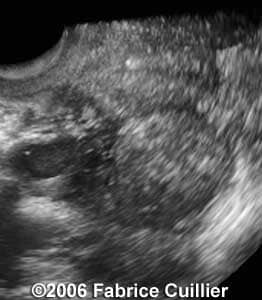

These are some cases of ectopic pregnancy (GEU) using the 2D and 3D scans.

Case 1